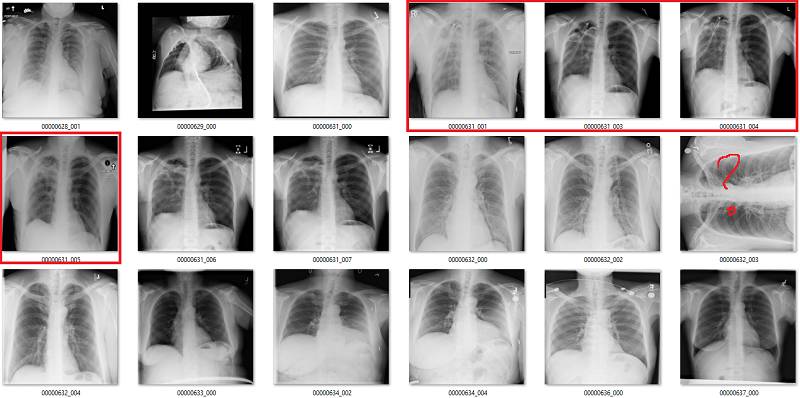

气胸(Pneumothorax)

气胸是指在肺部周围的胸膜腔空间有气体。这可能导致肺部瘫痪,因此它是非常严重的病变。但实际上,气胸在 X 光影像上非常微小,经常会被人忽略掉。

初次看来,标签似乎非常有效。在这 18 个样本中,只有用橙色标出的那张影像有点问题,这也可能是因为我没在诊断环境下查看肺部影像的原因。

但是绿框也有点问题,因为这些病人已经使用胸腔引流治疗过气胸。因此,现在有以下两个问题:

这并不是医学上重要的问题,我们希望避免气胸未被诊断出的错误,而这些图像标签确实没有犯这种错误。

如果很多影像都通过胸腔引流治疗,AI 系统将会学习识别胸腔引流而不是气胸。模型训练时的大多数图像样本批量完全可能包含有胸腔引流的气胸。

纤维化

我们已经看到,纤维化的标注准确率非常低。在这些影像中,红框是不正确的标签,橙框是我不确定的标签。在胸腔积液和固结中可能也会出现纤维化,但这些是影像无法告诉我们的。